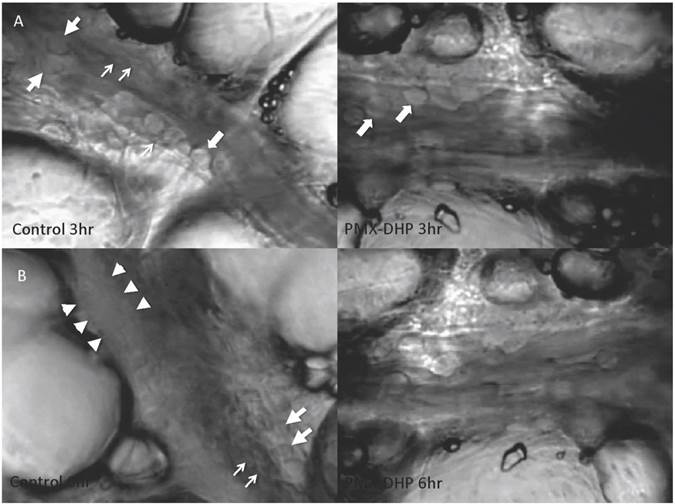

At three hours after LPS instillation, leukocyte adhesion to the endothelial surface of the venule was observed in both the control and the PMX-DHP groups. In addition to leukocytes, platelets had stuck to the endothelium and leukocytes in the control group, whereas, minimal sticking was observed in the PMX-DHP group (Fig. 1A). These changes increased over time, and the lining consisted of adherent leukocytes and platelets covering the surface. As a result, the vascular lumen became significantly narrow at six hours in the control group. Although the number of leukocytes increased, the lining was not observed in the PMX-DHP group and the blood flow was better maintained (Fig. 1B).

Status of lung microcirculation at 3 and 6 hours after LPS inhalation. At 3 hours (row A), in addition to the adherent leukocytes (large arrows), platelets had stuck to the endothelium and leukocytes (small arrows) in the control group (left). Leukocytes, but very few platelets, adhered to the endothelium in the PMX-DHP group. (Objective lens with a magnifying power of ×20). At 6 hours (row B), a thick lining formed from adherent leukocytes, platelets and fibrin deposition (between the arrowheads) had narrowed the vessel cavity in the control group. The large arrow indicates a leukocyte, and the small arrows indicate platelets. Blood flow was maintained in the PMX-DHP group. (Objective lens with a magnifying power of ×20)